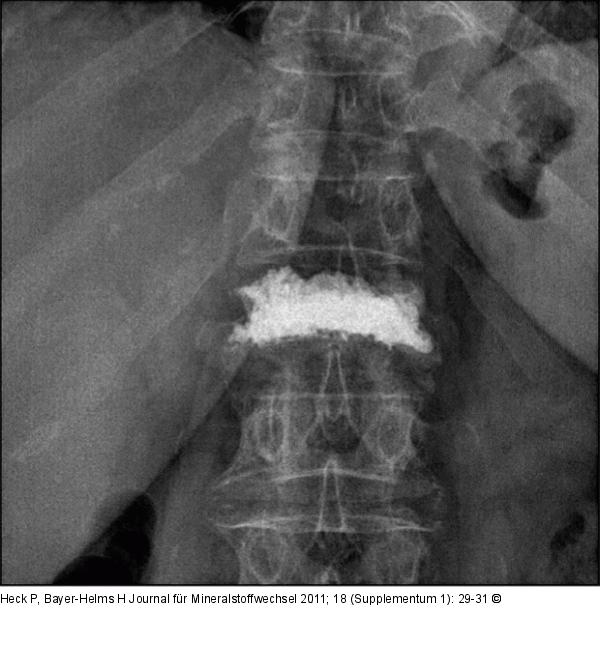

Abbildung 5: Lumbar vertebra First lumbar vertebra, anteroposterior view, after 3 months |

Abbildung 5: Lumbar vertebra

First lumbar vertebra, anteroposterior view, after 3 months |